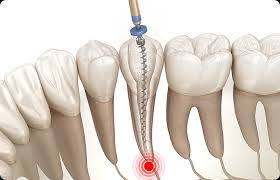

신경치료 후 치아는 내부 구조가 약해져 쉽게 깨질 수 있습니다. 크라운은 이를 보호하고, 씹는 기능과 심미성을 복원해주는 중요한 치료 단계로, 선택이 아닌 필수입니다.

1. 치과 신경치료란?신경치료(근관치료)는 치아 내부의 손상된 신경(치수)을 제거하고, 그 공간을 소독한 후 밀봉하여 감염을 막는 치료입니다. 충치가 깊어져 신경까지 침범하거나 외상, 감염